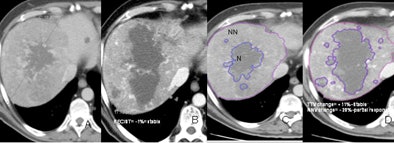

| Evaluation of therapy response in a 52-year-old living male with HCC showing a good clinical response to antiangiogenic therapy. Baseline CT scans (A,C) and six months post-treatment CT (B,D) show stable disease according to existing RECIST and TTV criteria but a partial response according to proposed NNV criteria (-28% reduction on NNV). |

The results varied based on the measurement method. Using RECIST criteria, about half of the patients showed response, while half showed disease progression. But based on total tumor volume, the majority of patients with stable disease end up in the progression category. Using NNV as a measure led to significantly more patients falling into the responder and partial responder categories, he said.